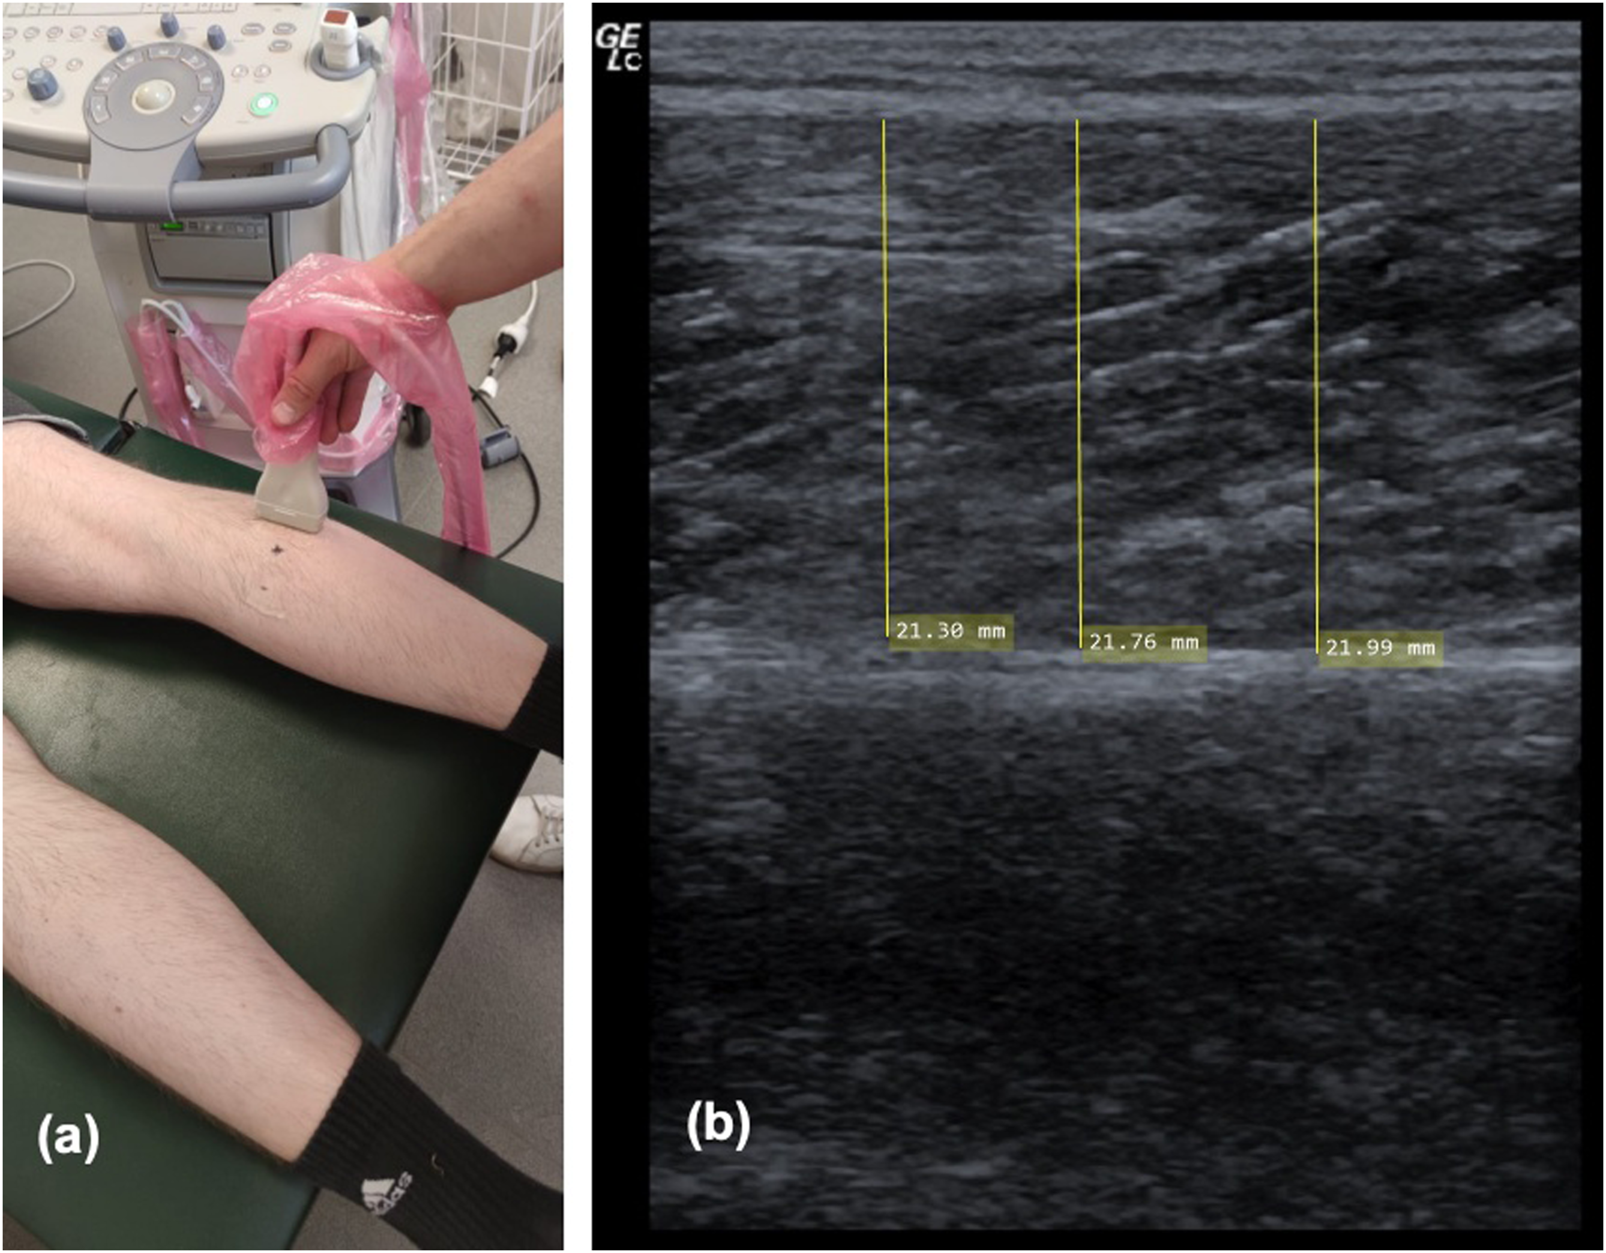

2.3.3 Ultrasonography for assessing muscle thickness

As previously described (Warneke et al., 2022c), ultrasonography was used to assess MTh, herein defined as the distance between upper and the deep fascia. Measures were obtained at pre- and post-study in both legs separately, using a two-dimensional B-mode ultrasound with a linear transducer (12, 13 MHz, Mindray Diagnostic Ultrasound System of 5 cm probe length). MTh was determined in the lateral (MThL) and medial (MThM) heads of the gastrocnemius. For this assessment, each participant laid in a prone position with their legs completely extended and feet hanging off the end of a table; they were instructed to stay completely relaxed during imaging. Measurements were obtained at 25 percent of the distance between the most lateral point of the joint space of the knee and the most lateral tip of the lateral malleolus. The superficial and deep aponeuroses were as parallel as possible to optimize visibility of the fascicles as continuous striations from one aponeurosis to the other. For measurement of MTh, the transducer was positioned at the midpoint of each muscle belly perpendicular to the long axis of the participant’s leg. The data for each measurement resulted from averaging three measurements across the proximal, central and sital portion of the produced image (Sarto et al., 2021) (see Figure 4). Two examiners performed two measurements per muscle independently from each other, blinded for the group. Thus, muscle thickness was evaluated by using MicroDicom (Sofia, Bulgaria). Reliability of sonography was determined previously with ICC = 0.95–0.97 (Warneke et al., 2022c).

FIGURE 4

Showing ultrasound procedure on the lateral head of the gastrocnemius (A) and one example of sonography measurement of the medial head of the gastrocnemius (B).